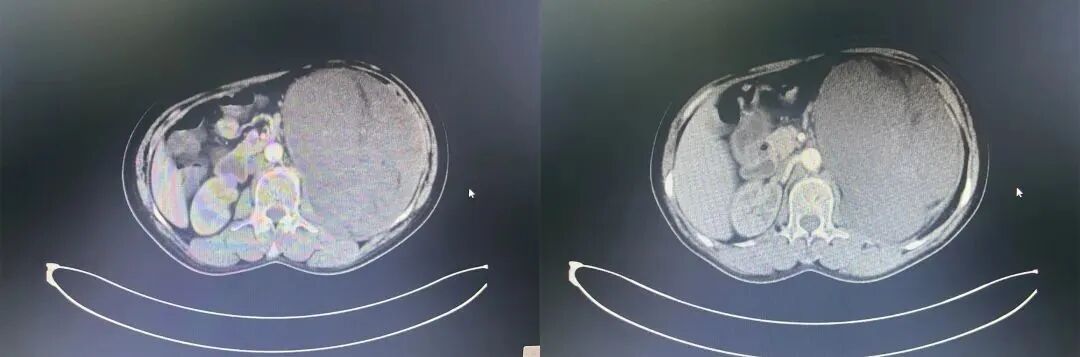

56岁的李女士,四天前突然发现左腹膨隆、腹胀,在家等候多日以为能有所好转,结果不光没有好转食量还下降了,于是来到济南市第三人民医院,以“腹部包块”收入消化内科,做了进一步的B超、CT等检查,都提示左侧腹膜后有一块巨大肿物,且大小为19×20cm,消化科建议转到泌尿外科,经诊断为:1.腹膜后肿瘤2.子宫平滑肌瘤3.肝囊肿4.肺结节5.乳腺结节。因考虑到肿瘤体积大,泌尿外科薛景新主任建议尽快手术治疗,在与病人和家属进行了充分沟通,说明了术中可能遇到的情况及应对措施后,最终同意行“腹膜后肿瘤切除+左肾切除术+腹腔粘连松解术”。

济南市第三人民医院泌尿外科团队在术前为李女士充分评估,多次与放射诊断科合作协调完成肿瘤血管成像(CTA/MRA),并联合进行多学科协作诊治,探讨病情并制定详细手术方案,因为此台手术难度、风险极高,遂邀请北京大学肿瘤医院泌尿外科张宁主任为李女士主刀。